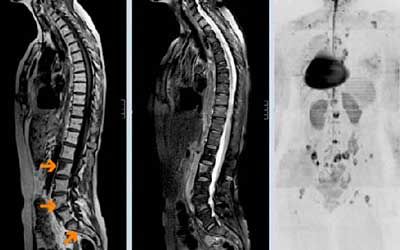

Множественные опухоли позвоночного канала

Множественные опухоли позвоночного канала — новообразования добро- или злокачественной этиологии, локализующиеся в оболочках или веществе спинного мозга или в полости позвоночного канала, где он находится. Чаще всего их диагностируют у пациентов обоих полов в возрасте от тридцати до пятидесяти лет, и крайне редко — у детей. Лишь 15% опухолей позвоночного канала локализуются в веществе спинного мозга, остальные поражают позвоночного канала.

Диагностика и лечение множественных спинальных опухолей

Специалисты ЦЭЛТ уделяют особое внимание точному определению локализации опухоли, её размеров, структур, вовлечённых в патологический процесс, и изменений, вызванных ею. Для этого они назначают пациенту комплексное диагностическое исследование, включающее в себя:

• магнитно-резонансную томографию;